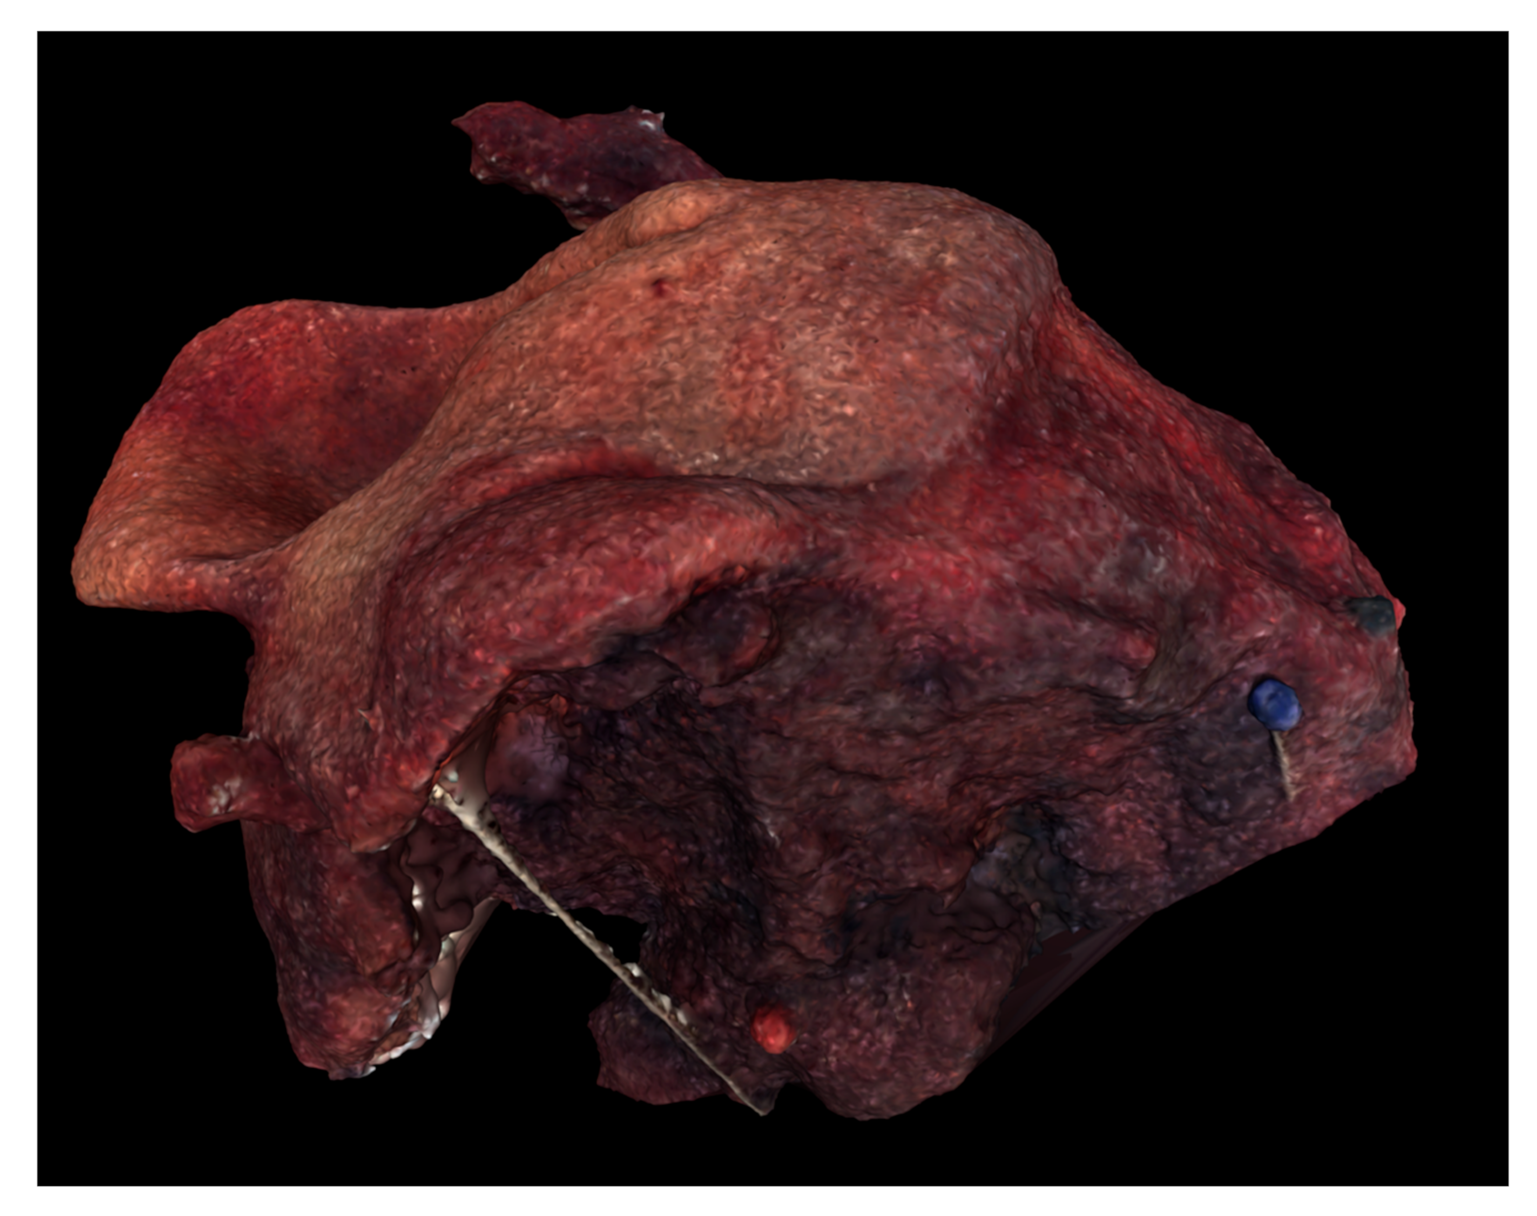

Figure 6.

Digital 3D model of Case 3 using Meshlab.

Digital and physical models of the surgical resection block were produced within one week of the operation. The 3D model dimensions were scaled up from the true dimensions of the resection block due to the small size of each tumor. Enlarging the dimensions of the model allowed for improved visualization of surface topography and anatomical details. For Case 1, the model produced by binder jetting conveyed more information than the material extrusion model because of the added color texture made possible by binder jetting (Figure 7 and Figure 8). Using material extrusion, the model was made of simple ABS-like white polymer with less detail.

Physical 3D models of Case 1 (A), Case 2 (B), and Case 3 (C) printed via binder jetting.

Production time for printing of the 3D model ranged from two to nine hours and printing costs ranged from 25 to 140 EUR: 24.90 EUR/28.41 USD (Case 1), 38.20 EUR/43.59 USD (Case 2) and 141.00 EUR/160.89 USD (Case 3).